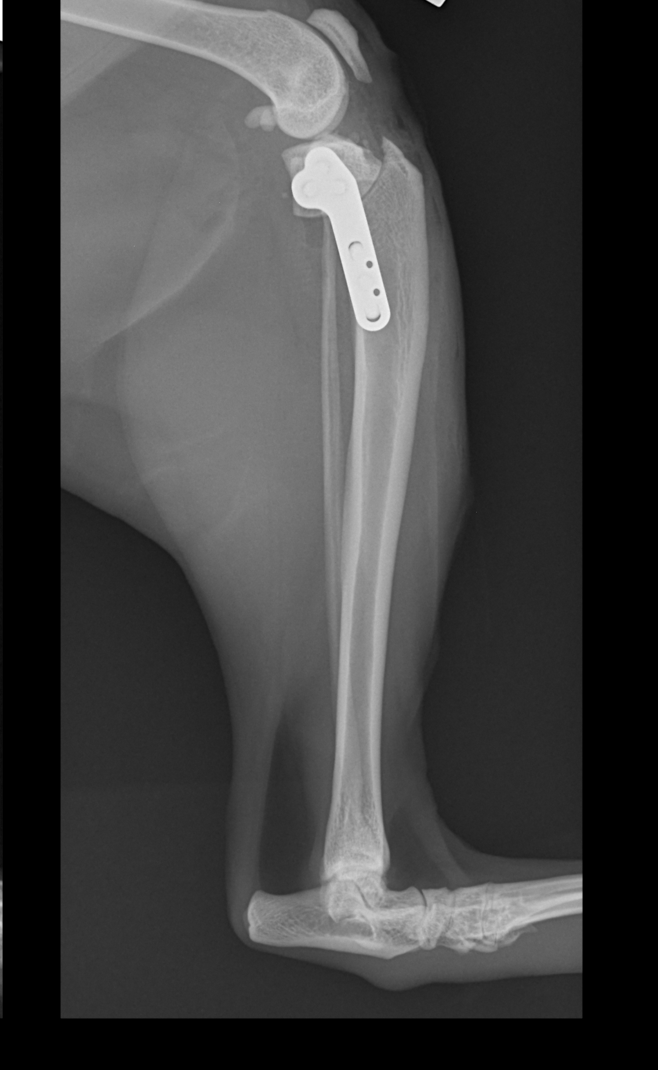

Wie beim Hund kann auch die Katze mit der TPLO-Technik operiert werden. Die Methode stabilisiert das Knie, lindert Schmerzen und ermöglicht eine schnelle Genesung.

Arthrex TPLO Platte

Wir verwenden Implantate der renommierten Firma Arthrex, die auch Implantate für die Humanmedizin herstellt. Hochpräzise Implantate, individuell angepasst an die Größe und Anatomie jedes Tieres.